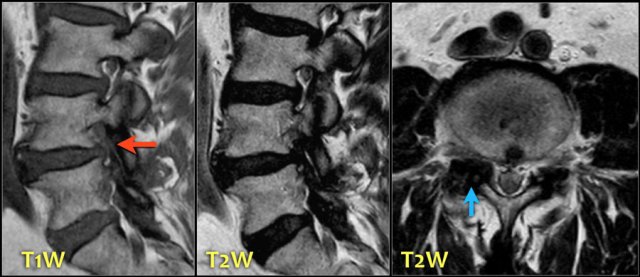

The signal intensity of a hernia on T1W-images is usually intermediate, while on T2W-images it can be a high signal fresh herniated nucleus pulposus or a somewhat older low signal intensity hernia.

Here a herniation with high signal (yellow arrow on transverse images) sliding through the annular tear and compressing the left L5 nerve (blue arrow).